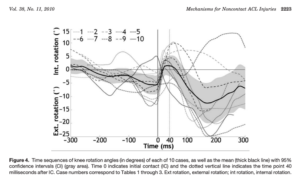

No caso de Murray, é possível identificar em vídeo a lesão com o joelho em valgo, que ocorre sem nenhum trauma direto. Em estudo retrospectivo que avaliou 1000 casos de lesões de LCA em atletas adolescentes, 67% das lesões no basquete também ocorreram sem contato direto, associadas à aterrisagem ou giro e mudança de direção (7). Este mecanismo de lesão do LCA no basquete também já foi discutido em uma série de 39 vídeos (8). Ainda com relação a biomecânica no momento da lesão, Koga et al (2010) evidenciou que após 40 milisegundos do contato inicial ao solo, ocorre um aumento da flexão (24º) e valgo (12º), acompanhados por uma rotação interna inicialmente (8º) seguida pela rotação externa (17º) com uma carga de 3,2 vezes o peso corporal (9) (Fig. 1 -3).

Fig. 2 – Reprodução da Fig. 4 de Koga H, et al. Mechanisms for noncontact anterior cruciate ligament injuries: knee joint kinematics in 10 injury situations from female team handball and basketball. Am J Sports Med. 2010